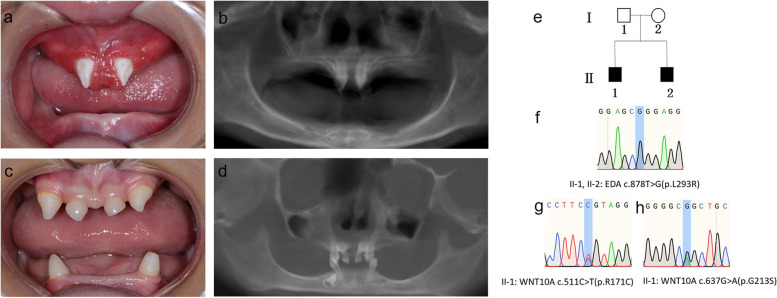

两名分别为11岁和8岁的亲兄弟因先天性牙齿缺失被转诊至同佳学基因具有合作关系的武汉大学口腔中心就诊。经患儿母亲及两名患儿本人签署知情同意书后,医护人员收集了两位患儿的病史资料,拍摄了相关临床照片,并采集了外周静脉血样本外送到佳学基因检测进行致病基因鉴定基因解码分析。这对兄弟被诊断为低汗性外胚层发育不良(HED),均表现出典型的临床特征,包括少牙(hypodontia)、毛发稀疏(hypotrichosis)、少汗(hypohidrosis)以及面部发育异常(facial dysmorphism)。有趣的是,哥哥的牙齿发育不全明显比弟弟更为严重。哥哥下颌完全无牙,仅保留上颌两颗中切牙;而弟弟则仍有部分前牙萌出。体格检查显示,这对兄弟均表现出头发稀疏、牙齿缺失及汗腺发育不良(图1a-d)。两人均具有X连锁低汗性外胚层发育不良(HED)的典型面容特征:鞍鼻、嘴唇厚大、下颌尖翘以及眼周黑眼圈。

口腔检查及锥形束CT(CBCT)扫描结果提示,哥哥(II-1)的所有乳牙及大多数恒牙均先天缺失,仅保留两颗锥形上中切牙(#11、21)(图1a-b)。由于下颌牙列完全缺失,他无法正常咀嚼或建立咬合关系。

弟弟(II-2)尚保留6颗乳牙(#51、53、61、63、73、83)及3颗恒牙胚(#11、21、43)(图1c-d)。

图1:HED兄弟患者的牙齿特征与面部表现

a-b:**兄长(II-1)**的口腔状况及全景X线片。

c-d:弟弟(II-2)的口腔状况及全景X线片。

e:家系图,黑色方块代表HED患者。

f:DNA测序图谱显示两位兄弟(II-1,II-2)携带EDA基因杂合变异c.878T>G(p.L293R)。

g-h:兄长(II-1)同时携带两个WNT10A基因杂合变异:c.511C>T(p.R171C)和 c.637G>A(p.G213S)。

母亲临床表型正常,未出现毛发、汗腺或牙齿相关异常。WES检测显示其为EDA基因c.878T>G杂合变异及WNT10A基因c.511C>T杂合变异的携带者。上述结果均经Sanger测序验证(图1e-h)。